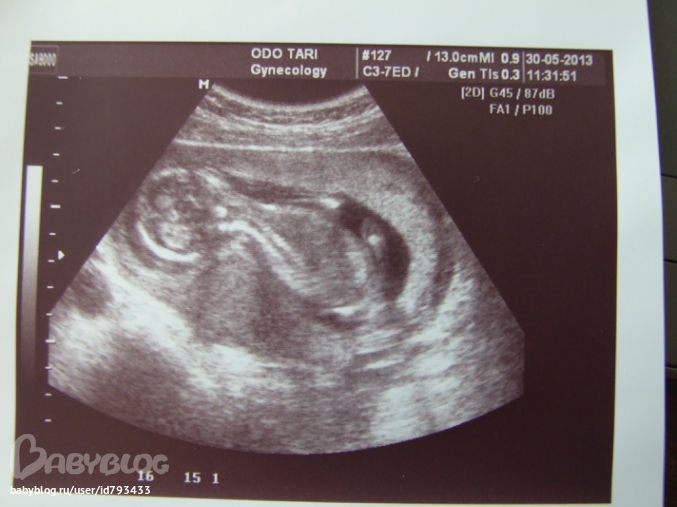

Знакомьтесь, это - Я живу у мамы в животике!

Цикл от 7.02 (счастливый)УЗИ на 16-той неделе. Вот какие мы уже!!! Наши размеры:

бипариетальный размер головки: 31 мм (15 нед.5 дней)

окружность живота: 102 мм (15 нед. 1 день)

Длина бедра: 19 мм (15 нед. 2 дня).

ЧСС - 152 уд/мин.